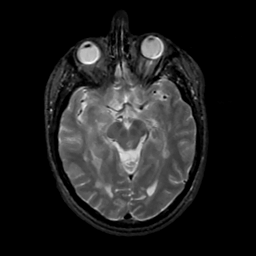

MR Study #2, February 17, 1991 -- Slice #21

[Home][Help][Clinical][Tour 1][Tour 2] Slice 21